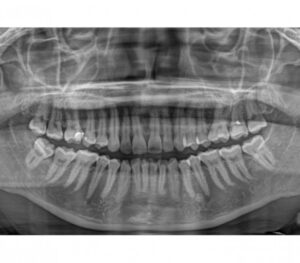

معمولا در جلسه ی اول مراجعه، دندانپزشک رادیوگرافی مخصوصی را برای شما تجویز می کند.

اولین گرافی جهت بررسی وضعیت کلی دندان ها و یک شمای کلی از ناحیه ی بی دندانی و ارتباط آن با سایر بخش ها و نواحی آناتومیک ،تصویربرداری پانورامیک که به آن OPGهم می گویند می باشد.

تصویر رادیولوژی <yoastmark class=

این نوع تصویربرداری یک نمای دو بعدی از وضعیت دندان ها و فک شما در اختیار دندانپزشک قرار می دهد.